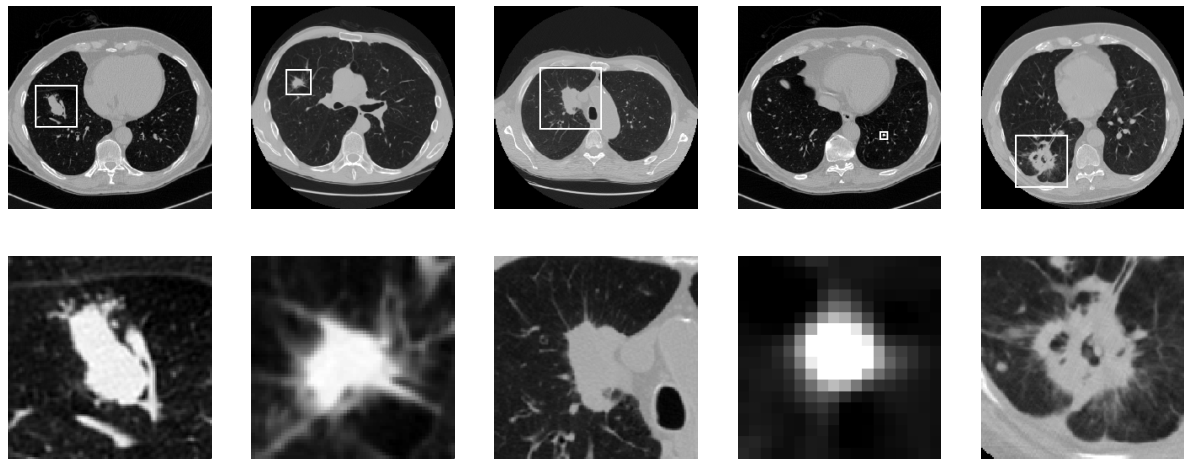

- 不同肺结节形状差异大,与正常组织难以区分,如下图。有时候医生也难以确定。